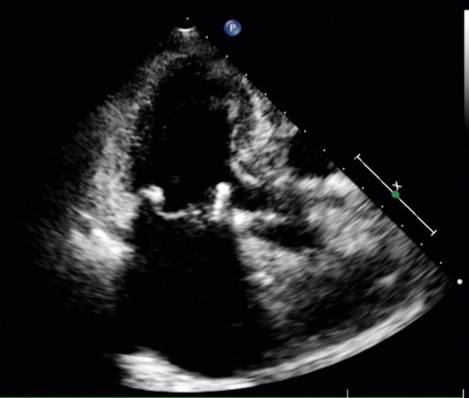

心超(2015-10-26)LA 4.6 (左右径×上下径:5.5×6.2)RA(左右径×上下径:3.7×5.0)RV2.2 LV 4.5 LVEF 0.47 TR 2.56(PG=26mmHg)心脏人工起搏器安装术后 二尖瓣人工生物瓣置换术后 双心房扩大 左室壁增厚 主动脉瓣钙化伴轻度关闭不全 三尖瓣轻度关闭不全 心功能降低 心包积液。

随访